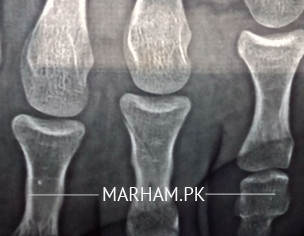

can any Dr please confirm if there's any bone fractured in this x-ray?

There is a fracture of the proximal phalanx of your fourth toe.

It is not displaced, you just need a soft shoe and buddy taping of your toes.

Yes, there is a fracture. If there is pain on put weight, I'll advise you to get a POP backslab. It will heal in 4 weeks and avoid weight bearing

yes there is hairline fracture of your bone. book appointment for further evaluation and treatment.

yes .there is hair line fracture of the 4 th toe. ghe treatment is above ankle pop cast till the tipa of toes..non weight bear for 4 wks.also keep your foot eleviated.so go near orthopedic specialist for pop cast